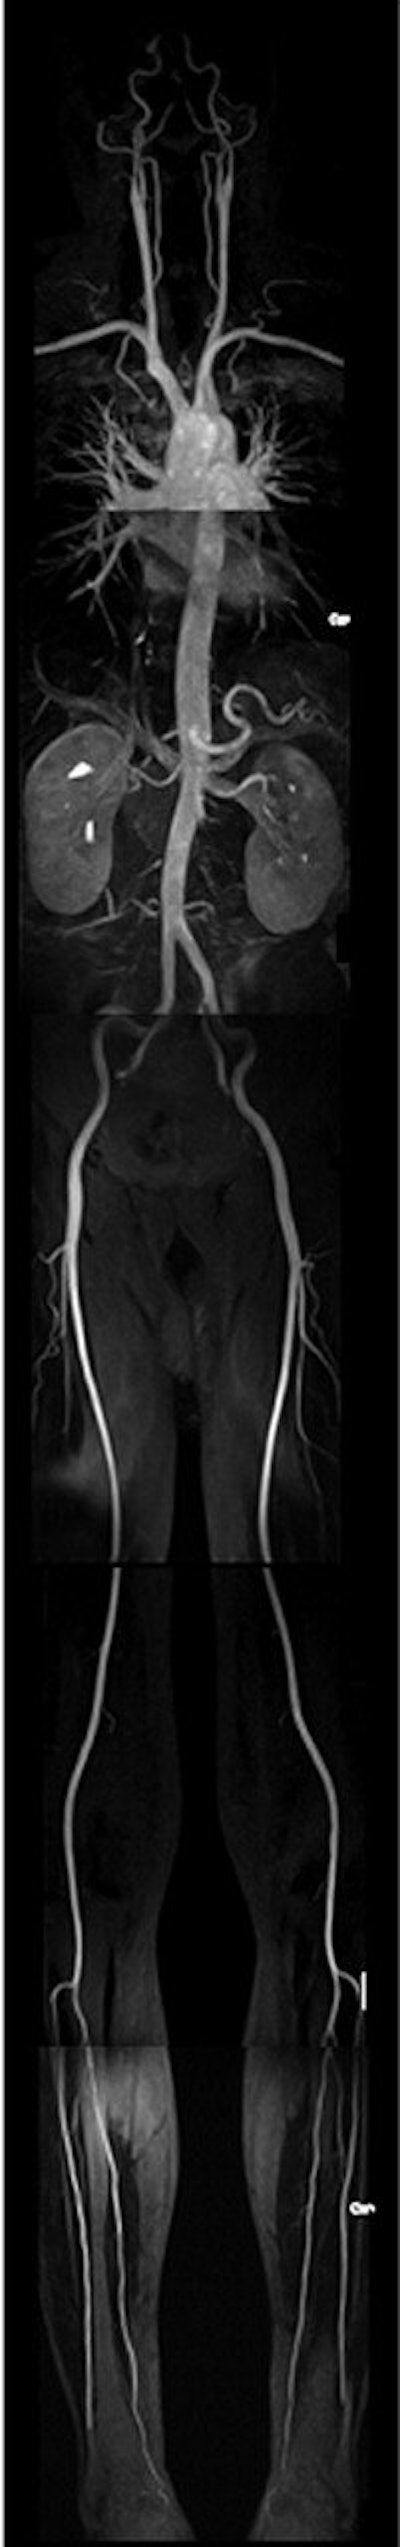

MR angiography

MR angiography was based on five slightly overlapping 3D coronal datasets (64 sections each) acquired in immediate succession using a 3D FLASH sequence. Each dataset was collected over 12 seconds, with the first three using the breath-hold technique.

After conventional test bolus timing with 1 mL at 1.2 mL/sec for individual assessment of circulation time, a 1-molar gadolinium-based contrast agent (gadobutrol, Gadovist 1.0, Schering, Berlin) was administered at a dose of 0.2 mmol/kg of body weight for arterial enhancement. The contrast material was diluted with saline solution to a total amount of 60 mL. Then, a biphasic contrast injection protocol was used: a first flush of 30 mL at 1.2 mL/sec and a second flush at 0.7 mL/sec, followed by a saline flush of 20 mL at 0.7 mL/sec. No venous compression was used, the authors wrote.

Whole-body MR allows rapid evaluation of the lower peripheral arterial system (AJR, June 2004, Vol. 182:6, pp. 1427-1434). However, one of the drawbacks of MRA is that lumen of the coronary arteries is not assessed. "Even though several techniques have been proposed, none has gained clinical relevance," the authors stated.